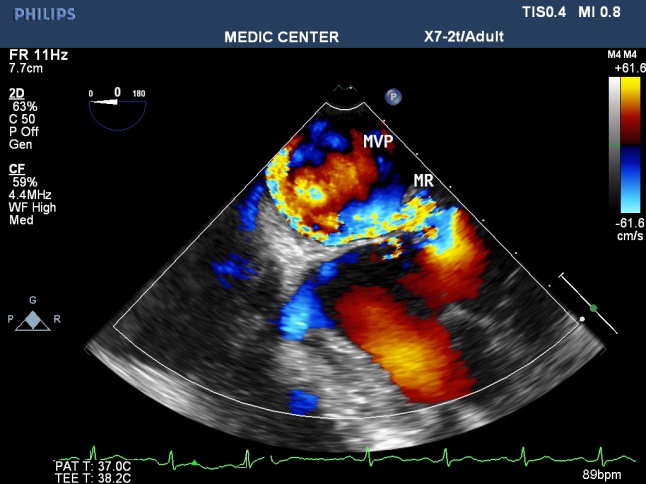

Among patients with mitral regurgitation, MVP accounts for the majority of our patients, fibroelastic disease and Barlow type of MVP were seen (Figures 18-21).

Figure 18. 2DTEE 90₀ plane visualizes a severe MR with excentric jet radiating into LAA

Figure 19. RT-3DTEE notes protruding PML viewed from LA side

Figure 20. Excentric jet MR due to Flail MV

Figure 21. Live 3D shows the severe MR